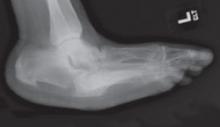

Acute CN is a clinical emergency characterized by pain, warmth, and erythema—making it clinically indistinguishable from cellulitis, osteomyelitis, or gout. Blood tests, including a white blood cell count, sedimentary rate, and uric acid level, may be necessary for diagnosis, as well as radiographs or magnetic resonance imaging. Treatment is long-term (4-6 months) immobilization of the joint to prevent further destruction,10 and bisphosphonates for pain during the acute phase.11 Untreated CN typically results in a rocker-bottom foot deformity (FIGURE) that puts patients at greater risk for plantar ulceration.

FIGURE

Rocker-bottom foot deformity

This radiograph reveals extensive collapse of the inner arch and a “rocker-bottom” foot deformity, the result of untreated Charcot neuroarthropathy.